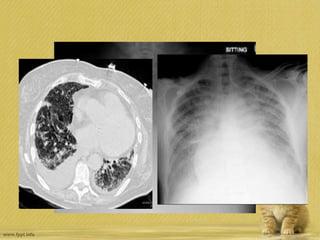

• 65 yaşında AML tanısı ile kemoterapi alan erkek hasta, ani gelişen

hipoksemi ve solunum yetmezliği ile entübe edilmiş. %100 oksijen

desteği ile PO2 54 mmHg . CT bilateral buzlu cam ve alveoler

opasiteler